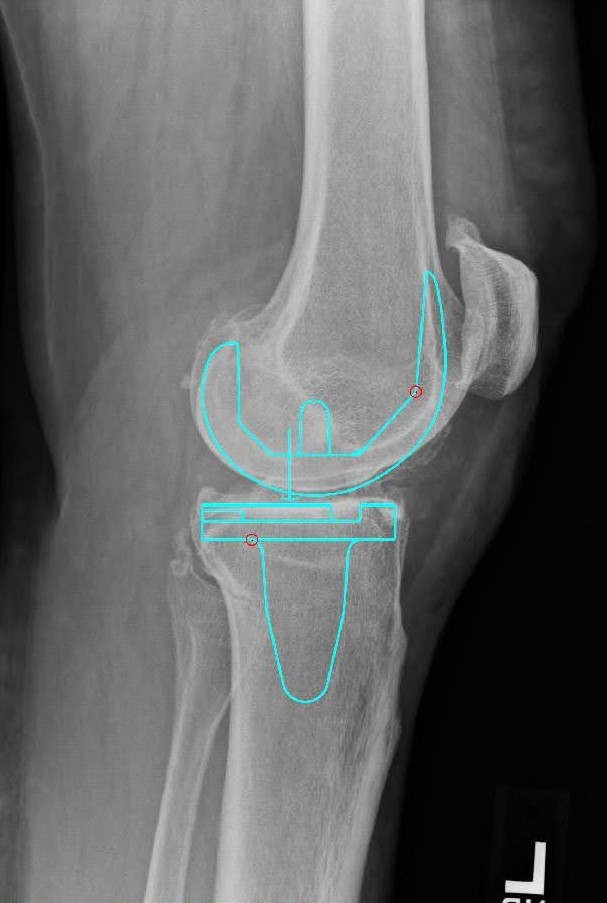

- Sistema Attune con un componente femoral de tamaño 4

- Tibia de tamaño 5 con inserto de retención cruzado de rodamiento fijo 4x7

- Botón rotuliano de polietileno de 38 mm